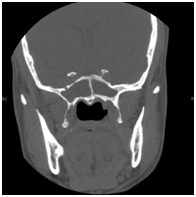

Allergic Fungal Rhinosinusitis AFS: Allergic fungal sinusitis is a non-invasive fungal sinusitis occurs in immunocompetent individuals in whom there is a strong inflammatory response to the fungal infection. This commonly results in a thick mucin that can be expansile and cause bony decalcification. There is also marked mucosal thickening and bone resorption due to the secretion of enzymes. Endoscopic examinations of these patients show the presence of allergic mucin and polyps. Major criteria for diagnosis by Bent and Kuhn their diagnostic criteria depend on the histologic, radiographic, and immunologic characteristics of the disease which include type 1 hypersensitivity, the presence of nasal polyposis, characteristic CT findings of heterogeneous hyperdensities that are often unilateral and asymmetric (Figure 3), an eosinophilic mucin and positive fungal stain or culture.16 AFS in sphenoid sinus can easily compress the cranial nerves. It was reported that cranial neuropathies develop in 10% of the sphenoid AFS with bone erosion. Treatment involves endoscopic sphenoidotomy to clear polyps and allergic mucin (Figure 4), and to restore the ventilation and drainage of sinuses with combination of medical therapy with corticosteroids. Anti-fungal treatment is usually not required. Histopathology is important to be obtained for the specimen which shows allergic mucin containing fungal components without any tissue invasion. These patients may get benefit from Immunotherapy post-op.

Figure 3 CT scan of bilateral sphenoid allergic fungal sinusitis./p>